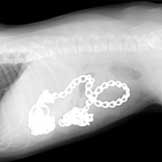

"They Ate What?"

Every year Veterinary Practice News holds a contest showcasing the craziest things patients have swallowed.